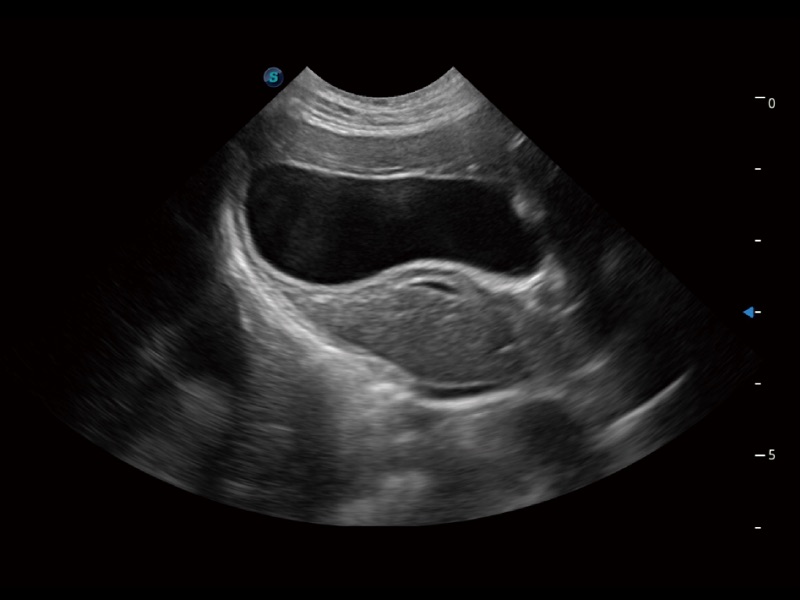

一键自动识别膀胱壁及自动测量膀胱容积,不受膀胱形状和大小的限制,帮助医生快速精准获得测量的数据。